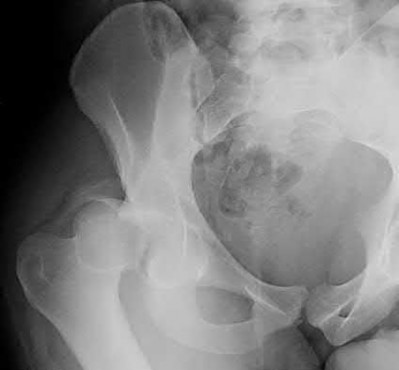

A 12-year-old obese boy presents with vague left thigh and knee pain. He is diagnosed with a Slipped Capital Femoral Epiphysis (SCFE) as seen in similar clinical scenarios.

During percutaneous in-situ fixation, unrecognized penetration of the guide wire into the hip joint occurs. What is the most likely specific complication resulting from this technical error?

Chondrolysis is a severe complication of SCFE characterized by rapid destruction of the articular cartilage. While it can occur idiopathically, its most established iatrogenic cause is unrecognized intra-articular hardware penetration. The 'approach-withdraw' fluoroscopic technique is required during pinning to assure pins are entirely intraosseous. Avascular necrosis (AVN) is usually due to damage to the epiphyseal blood supply (retinacular vessels) secondary to the initial displacement, forceful closed reduction, or posterosuperior pin placement.